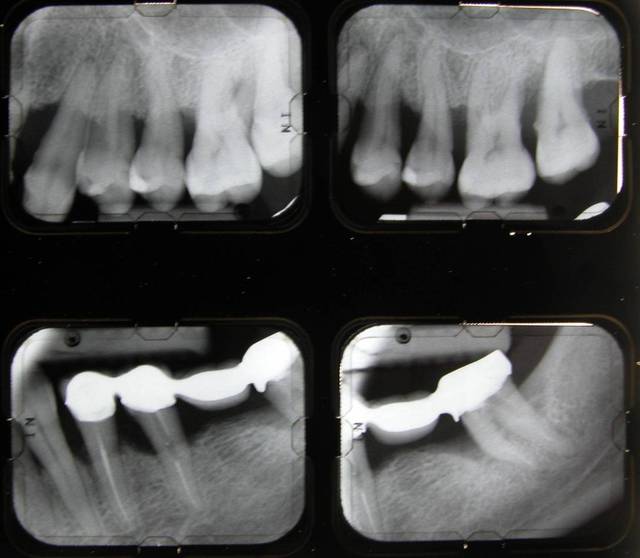

Voici le cas d'une patiente que j'ai traité pour une parodontite chronique.

Donc il s'agite d'une patient adressée par un confrère pour un avis paro avant un traitement ODf. La patiente a cinquante cinq ans. Elle fume des cigares, des problèmes d'hygiène. Je dignostique une parodntite chronique que j'ai traité en non chirurgical. La patiente est en observation avant d'entamer un traitement prothétique plutôt qu'ODF.

La consultation: DSCN 7002

1 mois après la consultation et motivation à l'hygiène: DSCN 7502

Le jour de la lithotriptie: DSCN 7030

6 mois après: DSCN 0013